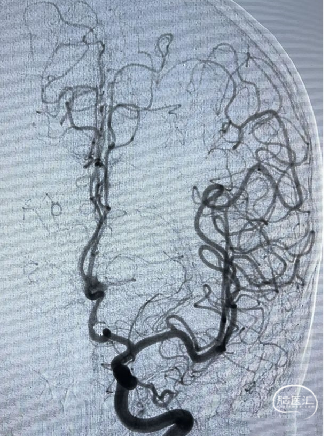

DSA:左侧大脑前动脉A2-A3动脉瘤(分叶状)